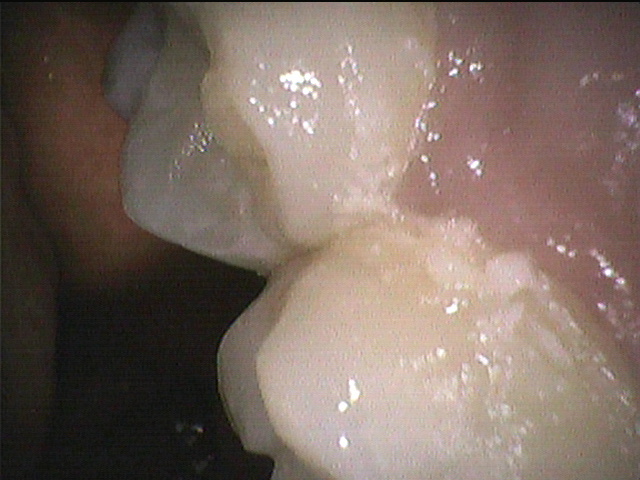

◎クリーニング前

上の奥歯の内側